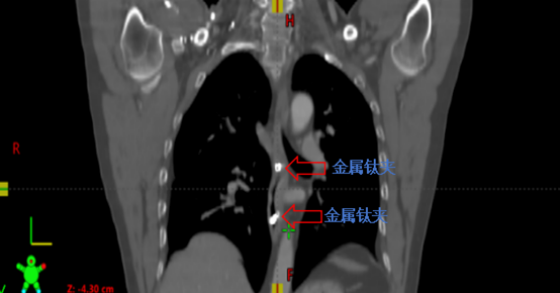

金属钛夹标记病变部位

接诊后,肿瘤科钟美佐主任同李军烽副主任医师结合患者既往病史和实际情况决定对病变部位实施放射治疗。考虑到患者食管病变较早,CT无法清晰显示病变部位及范围,患者曾经又接受过上段食管放射治疗,为进一步减少照射范围,准确定位肿瘤位置,肿瘤科联合消化内科,通过消化内镜在原位癌处附近植入金属钛夹标记物后再行增强CT,根据钛夹位置对病灶实施精准定位,尽可能的减少不必要的照射,降低患者放疗副作用的发生。目前高大哥已结束放射治疗,不适症状得到明显缓解。